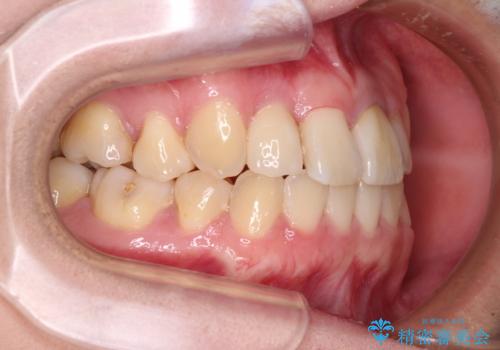

- 奥歯が痛いとのことで来院された患者様です。

上顎親知らず周辺の炎症と、神経組織の失活した歯の炎症による痛みが認められたため、親知らずの抜歯と根管治療を行いました。

根管治療を行った歯はクラウンによる補綴治療が必要となりますが、高校生の頃に行った矯正治療の後戻りも気になるとのことで、補綴治療を行う前に矯正治療を行うこととしました。

後戻りは軽度であり、インビザラインにて歯列を整え、その後にオールセラミッククラウンにて補綴治療を行うこととしました。